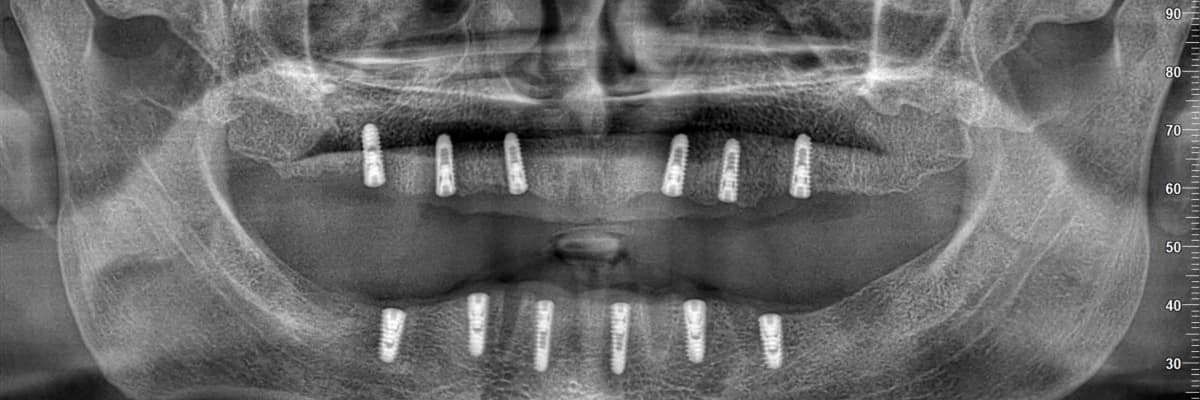

İmplant uygulamalarımız, operasyon öncesinde yeterli kemik seviyesi ve anatomik oluşumların klinik ve radyolojik olarak detaylı muayene edilmesiyle başlar. Planlama aşamasından sonra operasyon, lokal anestezi altında gerçekleştirilir. Yaklaşık 1,5 - 2 saat süren bu işlem sırasında, anestezinin etkisiyle hastalarımız herhangi bir ağrı hissetmemektedir.